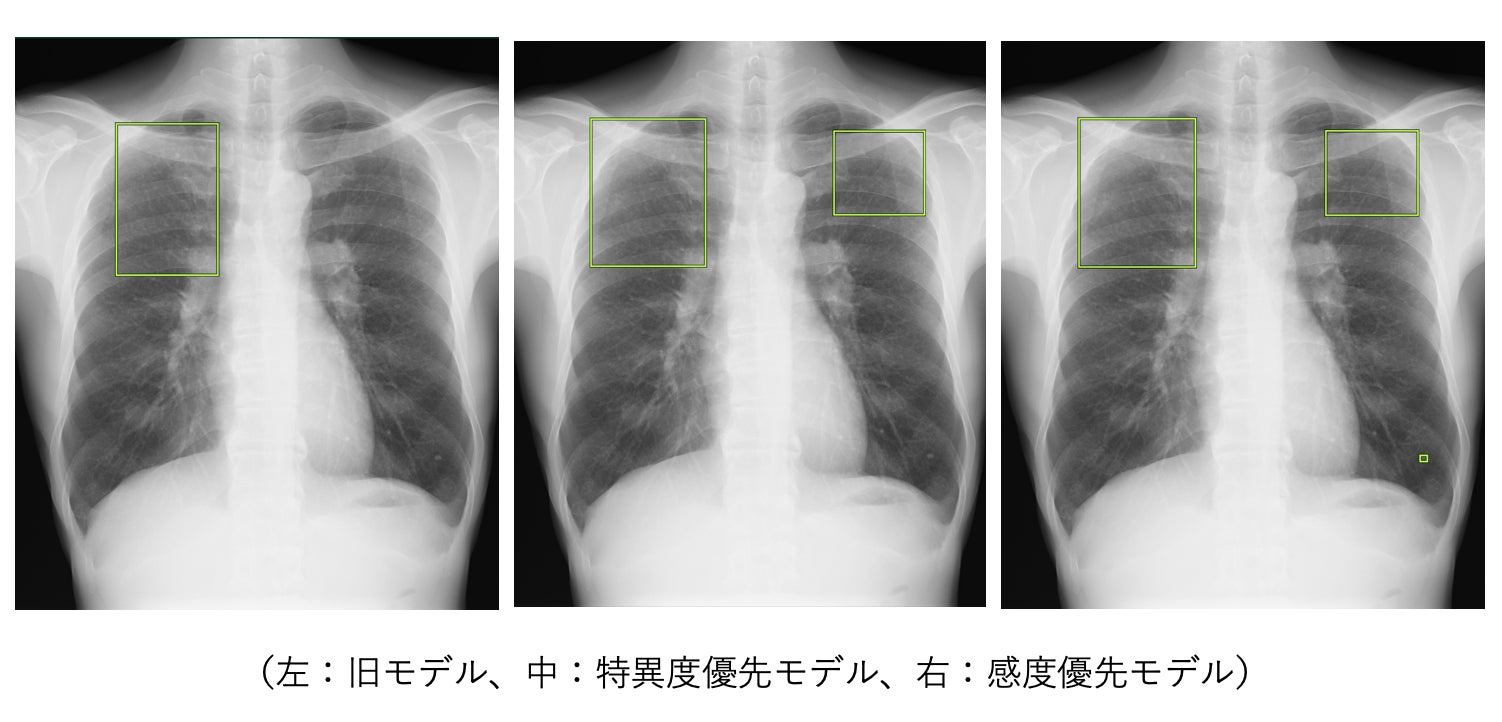

・事例①

感度優先モデル/特異度優先モデル双方において間質性陰影が疑われる所見の検出が改善し、感度優先モデルでは結節影が疑われる所見も検出している事例

・事例②

感度優先モデル/特異度優先モデル双方において旧モデルと比較し偽陽性が改善された事例

※ 該当箇所以外の表示を消すなど、実際の製品の表示とは異なる場合があります。